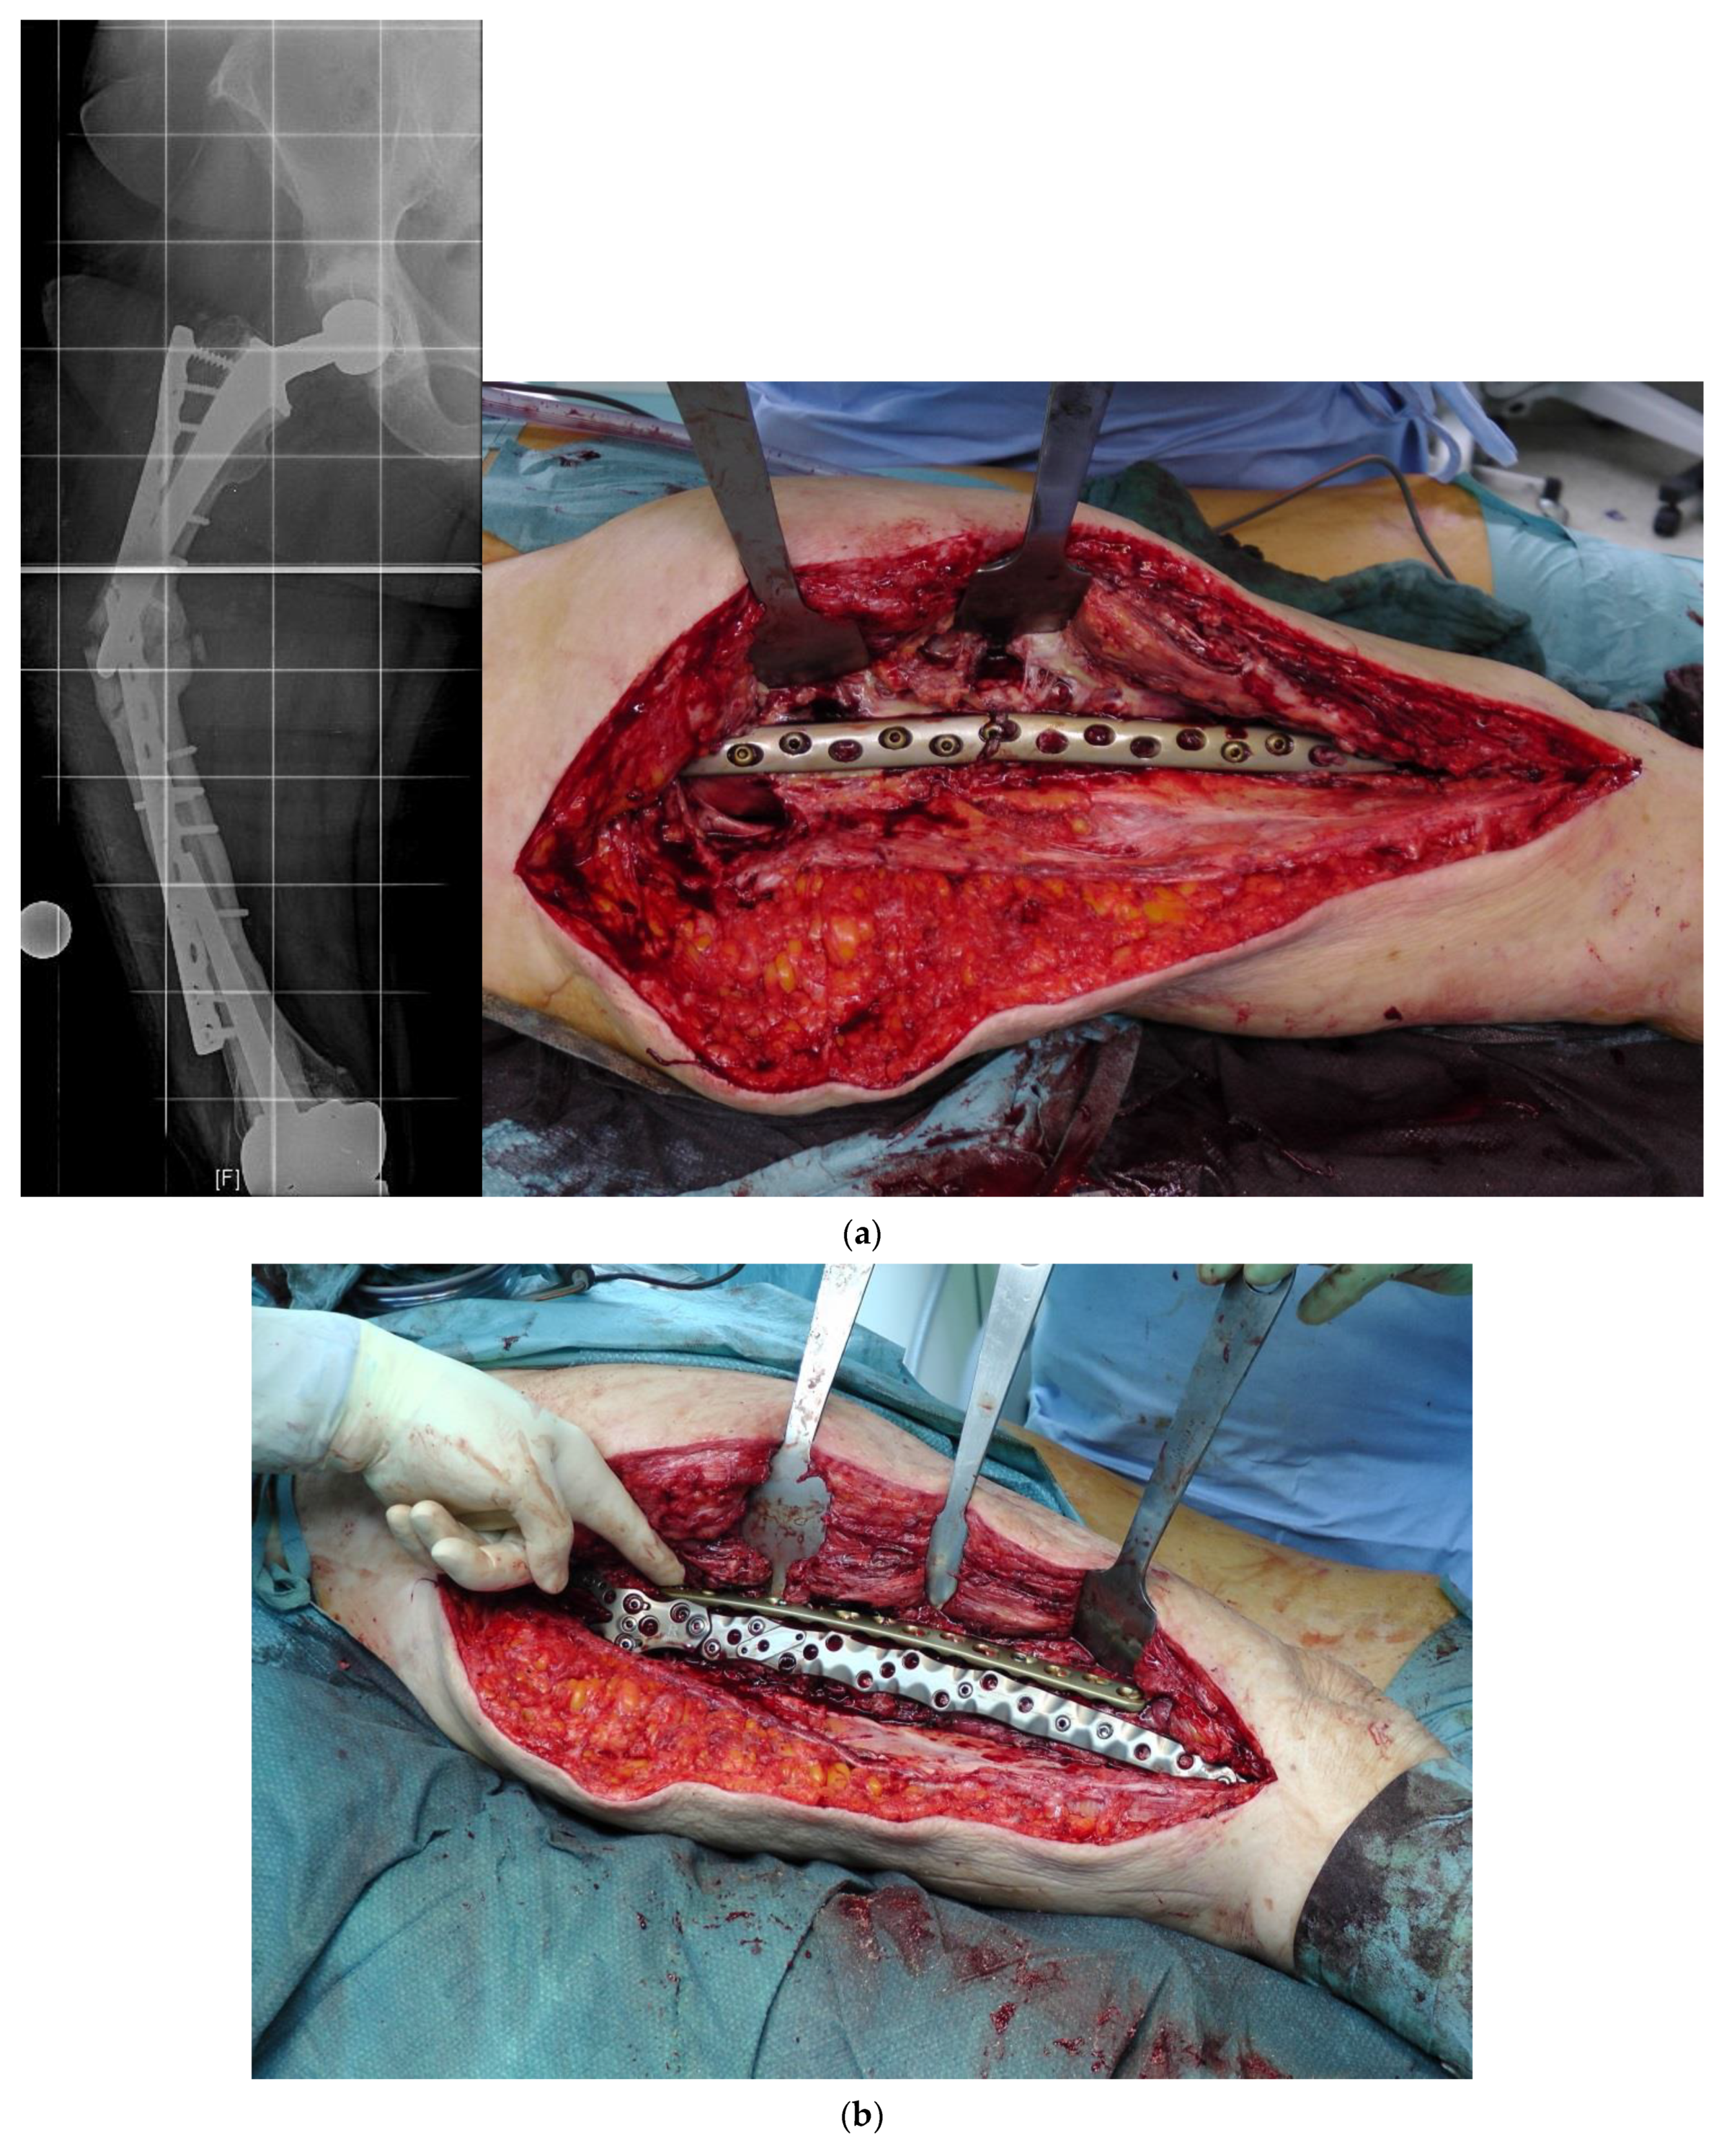

In revision cases and interprosthetic fractures, double plating is an alternative treatment option to avoid high-risk operations such as a total femur replacement. Figure 4 shows a successfully treated hypertrophic non-union after several interprosthetic re-fractures, using double plating in combination with autologous bone-grafting and growth factor application.

Figure 4.

(a) Interprosthetic hypertrophic non-union. Intraoperative situs showing the failed plate fixation and the non-union. (b) Intraoperative situs showing the double plating. (c) Double plating combined with bone-grafting and growth factor application. (d) Postoperative follow-up X-rays after 6 weeks, 12, and 24 months, demonstrating complete healing and remodeling of the fracture.